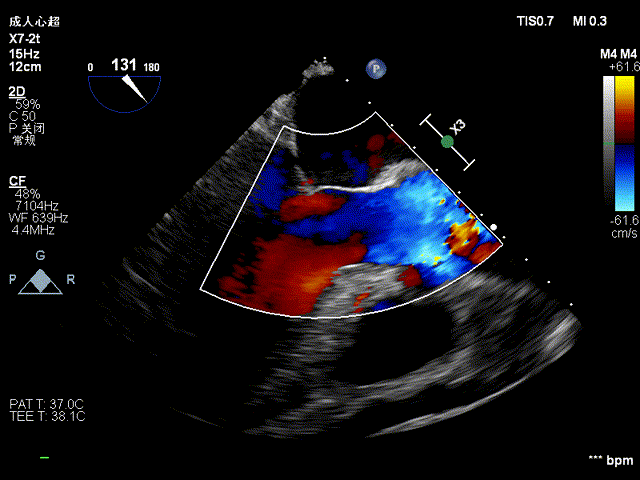

术前术后食道超声对比:

术前